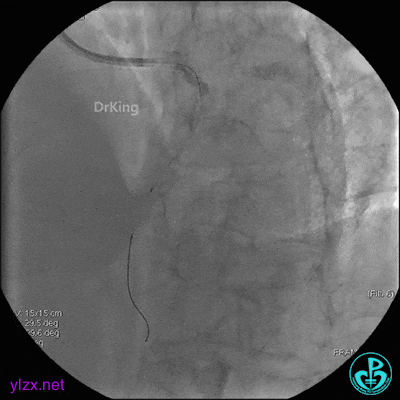

5 治疗过程

EBU指引导管到位,导丝通过闭塞段到达前降支远端,经指引导管冠脉内推注替罗非班6ml,前降支恢复3级血流,闭塞段局部残余狭窄严重,2.0×15mm球囊扩张前降支近端闭塞处后再次冠脉内推注替罗非班8ml。下台继续治疗。